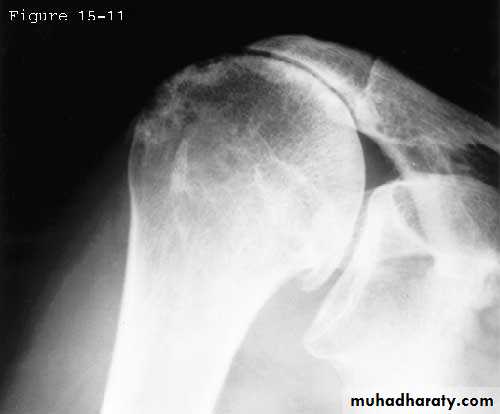

X- ray

-Erosion of greater tuberosity-Upward migration of humeral head

-Osteoarthritis of acromioclavicular joint